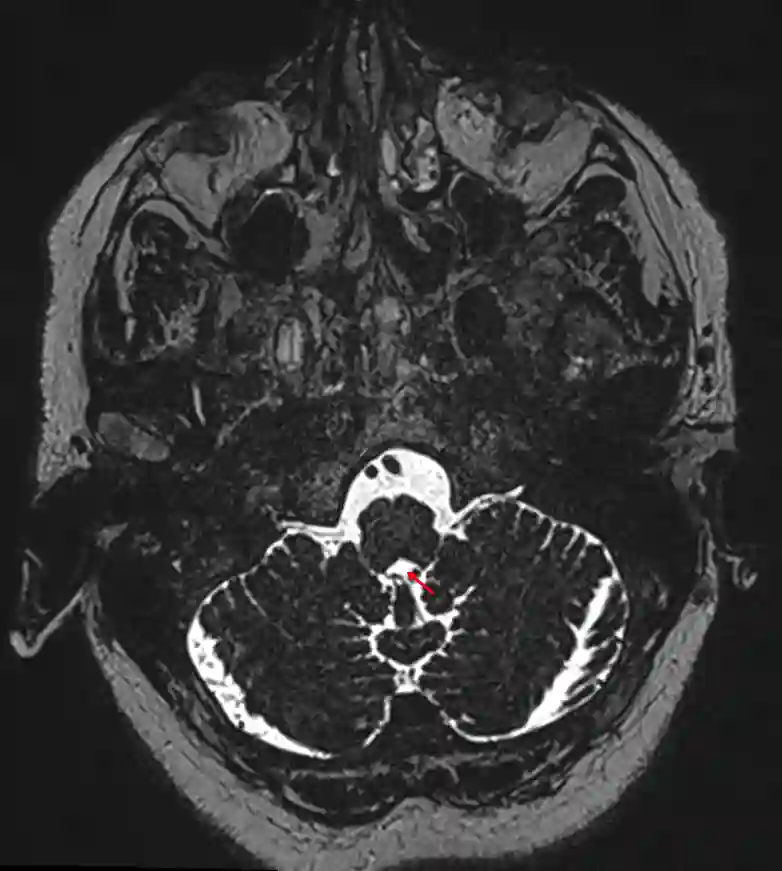

Foramen magendie im MRI

Axiale MRI CISS Sequenz mit Markierung des Foramen Magendii mit einem roten Pfeil.